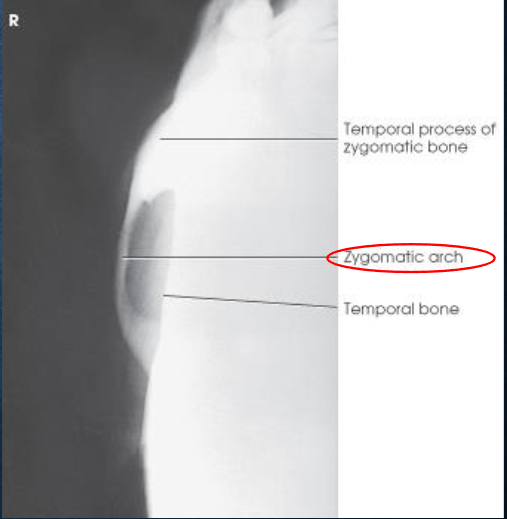

Tangential zygomatic arches image criteria

one zygomatic arch free of superimposition

arch not overexposed